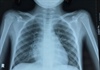

Bệnh nhân nói trên là một bé trai 11 tuổi, đến từ Phú Yên. Trước đó, ngày 4.7 bé nhập Bệnh viện Nhi đồng 2 với các triệu chứng bị ho ra máu với lượng lớn. Trong quá trình thăm khám các bác sĩ nghi ngờ bệnh nhân bị lao phổi nên chuyển qua Bệnh viện Phạm Ngọc Thạch (TP.HCM). Tại đây bệnh nhân được làm các xét nghiệm xác định lao song cho kết quả âm tính, CT Scan ngực nghi ngờ u thùy dưới phổi nên phải chuyển trở lại Bệnh viện Nhi đồng 2. Qua thăm khám, các bác sĩ đã phát hiện bệnh nhân bị túi phình động mạch phổi ở thùy dưới phổi phải, kích cỡ 20 x 18mm. Qua kết quả lâm sàng và xét nghiệm cho thấy bệnh nhân mắc chứng bệnhbehcet, là bệnh tự miễn hiếm gặp.